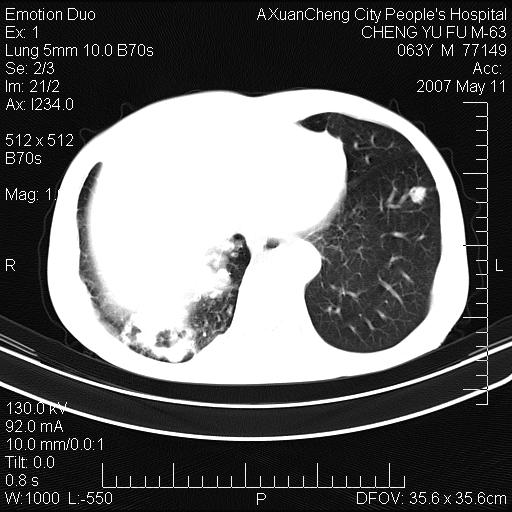

以下是引用小初学者在2007-5-11 19:32:00的发言:[br]1、首先考虑干酪性肺炎支气管播散[br]2、支气管肺泡癌待排

以下是引用zhangzhongshou在2007-5-11 19:30:00的发言:[br]细支气管肺泡癌可能性大。